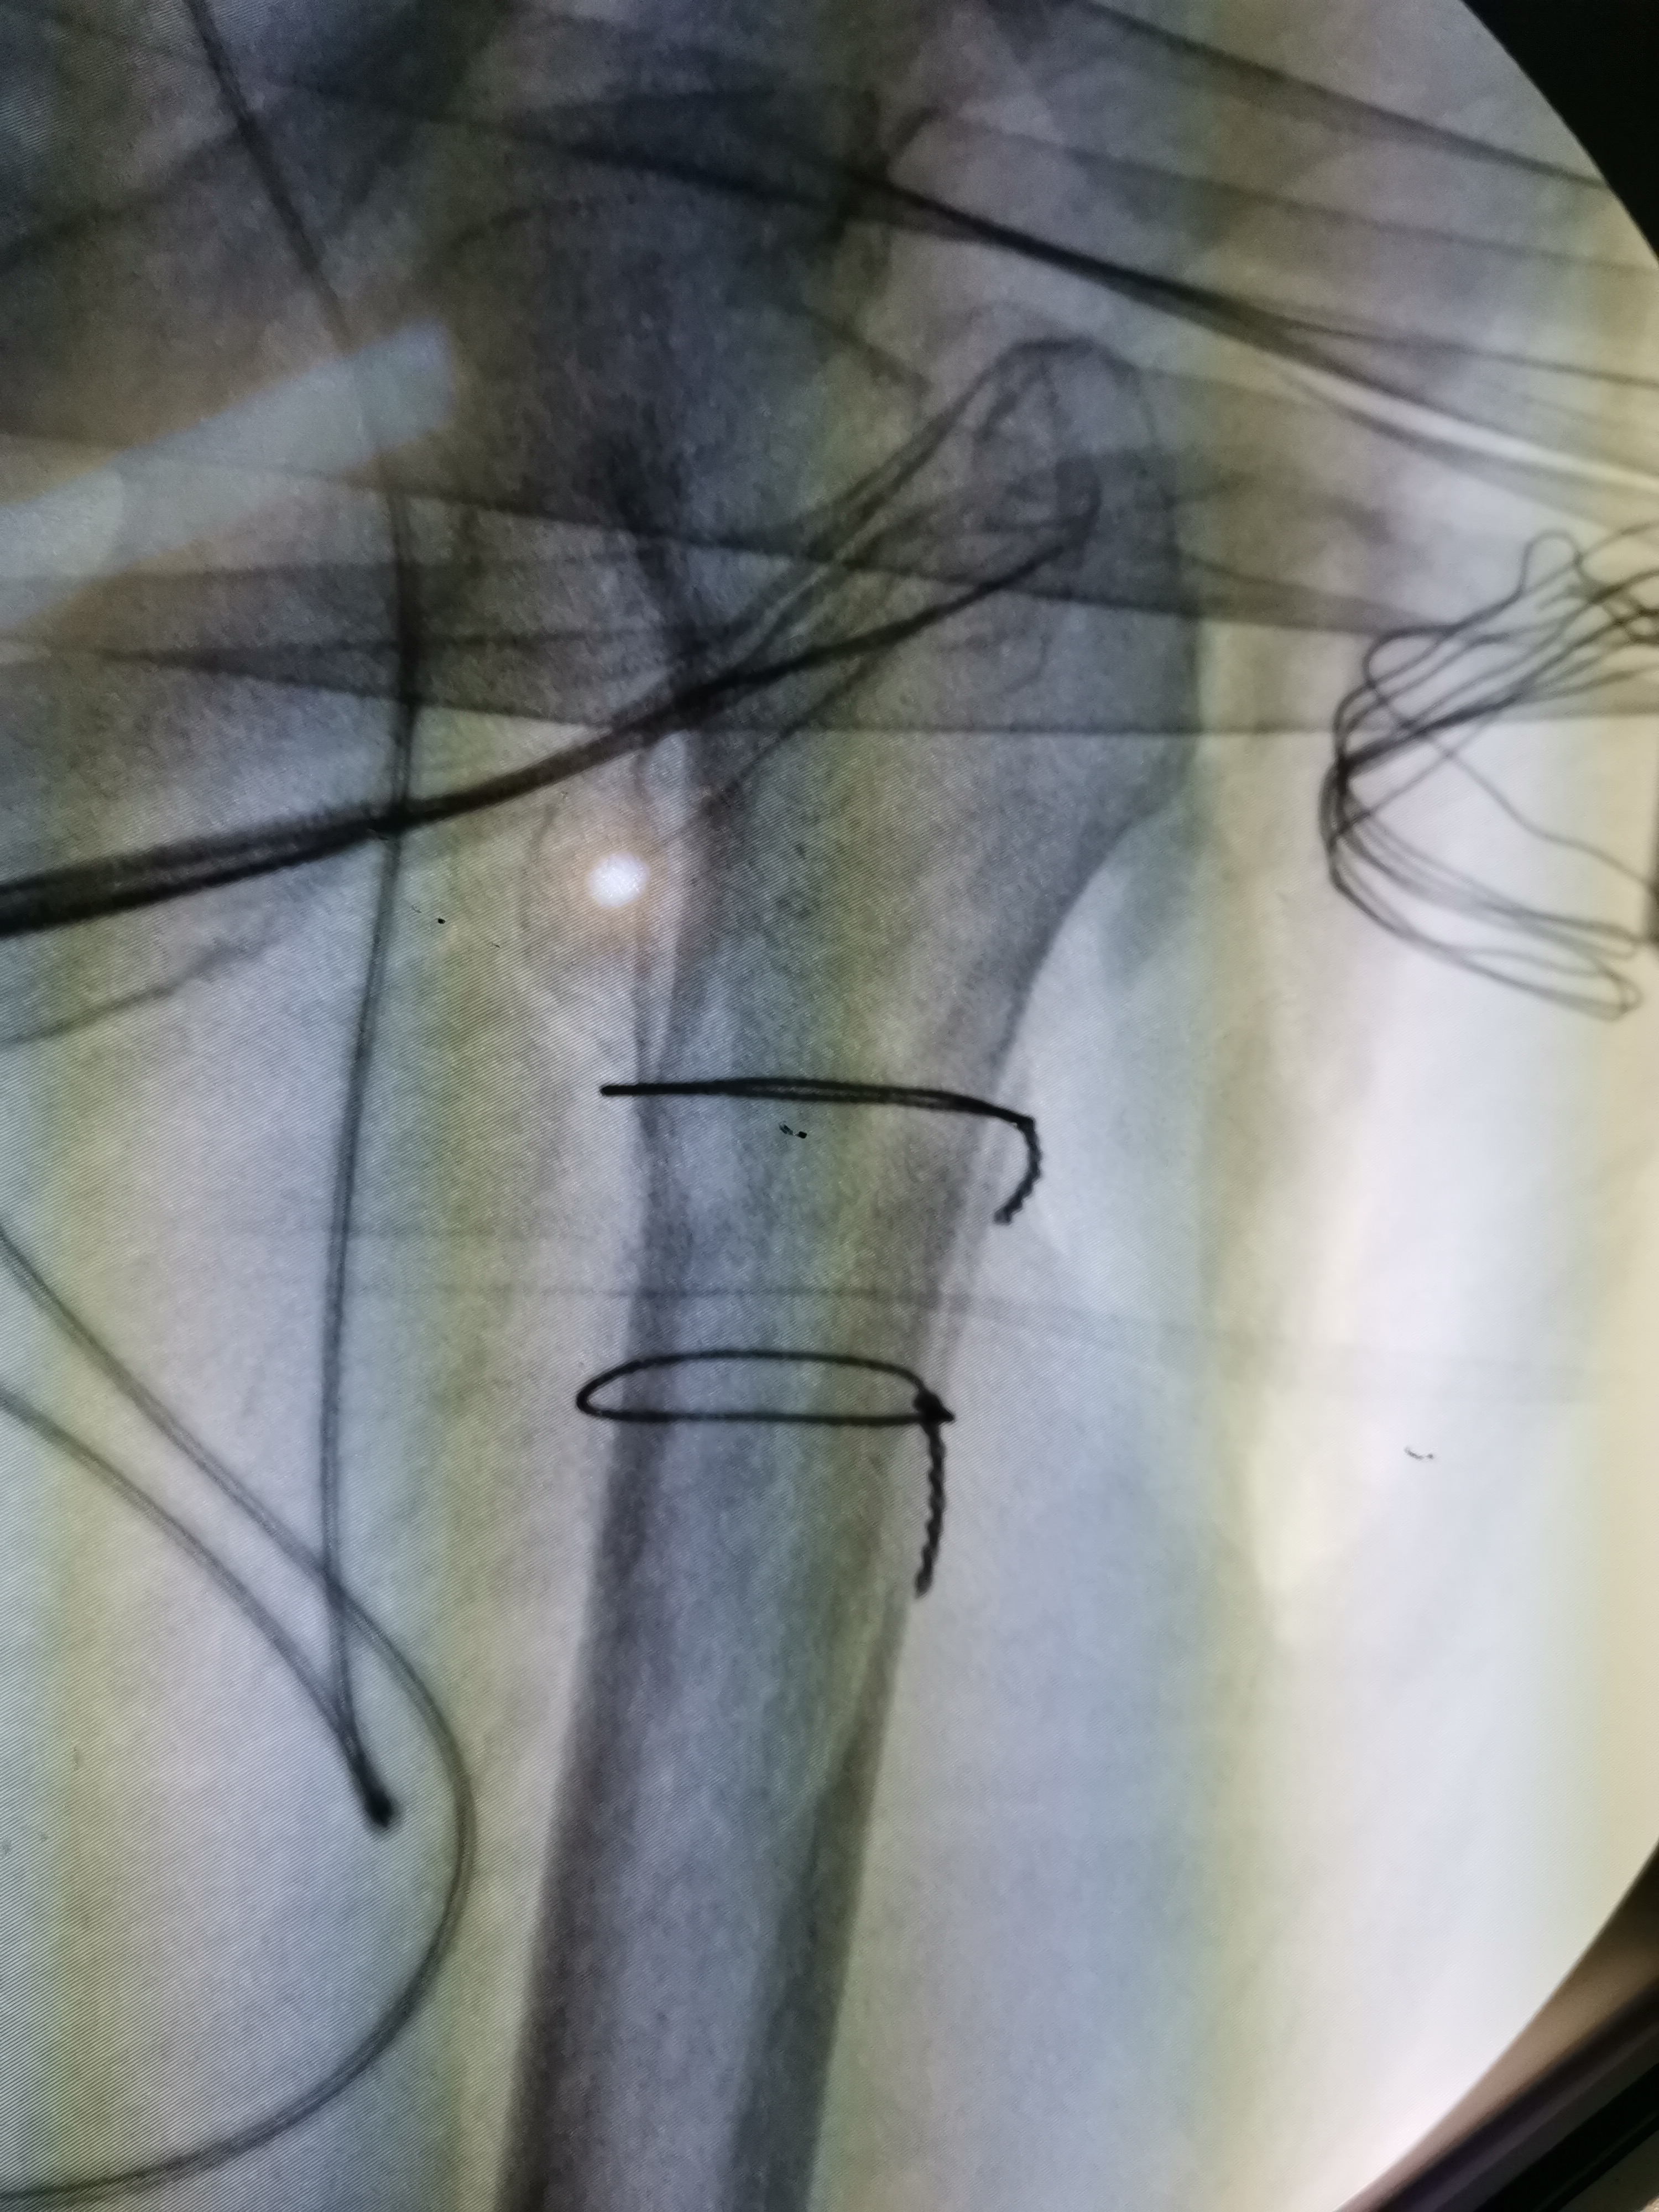

手法复位成功可以大大减少手术时间,避免皮肤切开后老人一边流血一边复位,从而增加出血量。在手法复位后,可以使用可移动的X线机进行透视,查看复位的情况,如下图所示,复位基本满意后就可以开始手术:

复位前后比较

手术首先切开皮肤,严重粉碎的股骨粗隆间骨折可以进行钢丝固定,这一步对于简单的骨折可以省略。该患者骨折粉碎,移位明显,必须进行钢丝的固定,在钢丝固定后我们欣喜地发现骨折已经完全复位:

钢丝固定